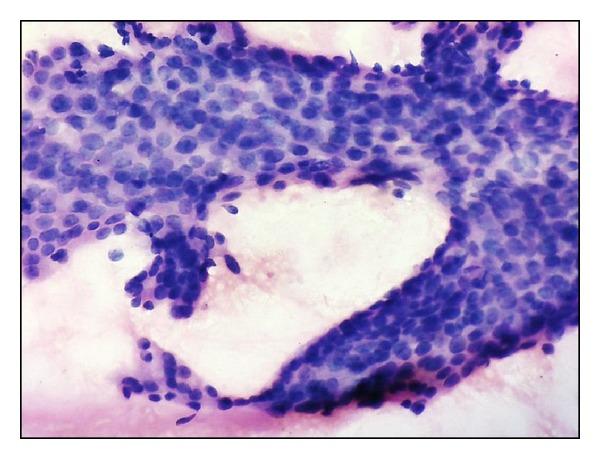

Background. Fine-needle aspiration cytology plays a major role in the primary diagnosis of breast carcinoma. Cytological grading of the smears can provide valuable prognostic information and aid in planning the management options. Aim. To evaluate various 3-tier cytological grading systems and to determine the best possible system which is reliable and objective for use in routine practice. Materials & Methods. 72 fine-needle aspiration smears of breast carcinomas were graded by two pathologists and compared with the histologic grading by Nottingham modification of Scarff-Bloom-Richardson method. Concordance and correlation studies were done. Kappa measurement of interobserver agreement was also done. Results. Robinson's method showed a better correlation (77.7%) and substantial Kappa value of agreement (κ = 0.61) with Bloom Richardson's histological grading method in comparison to the other methods, closely followed by Fisher's method. Fisher's method showed better interobserver agreement (84.7%, κ = 0.616) compared to the other systems. Conclusions. Robinson's method of cytological grading in fine-needle aspiration smears of breast carcinoma is simpler, multifactorial, and feasible, hence being preferable for routine use according to our study.

背景。细针穿刺细胞学检查在乳腺癌的初步诊断中起着重要作用。涂片的细胞学分级可以提供有价值的预后信息,并有助于制定治疗方案。目的。评估各种三级细胞学分级系统,并确定在常规实践中使用的最可靠、客观的最佳系统。材料与方法。由两位病理学家对72例乳腺癌细针穿刺涂片进行分级,并与采用诺丁汉改良的斯卡夫-布卢姆-理查森方法进行的组织学分级进行比较。进行了一致性和相关性研究。还进行了观察者间一致性的kappa测量。结果。与其他方法相比,罗宾逊方法与布卢姆-理查森组织学分级方法显示出更好的相关性(77.7%)和较高的kappa一致性值(κ = 0.61),其次是费舍尔方法。与其他系统相比,费舍尔方法显示出更好的观察者间一致性(84.7%,κ = 0.616)。结论。根据我们的研究,罗宾逊方法用于乳腺癌细针穿刺涂片的细胞学分级更简单、多因素且可行,因此更适合常规使用。